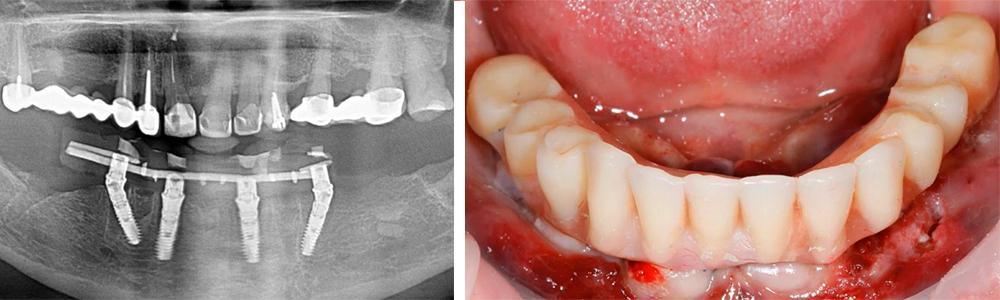

Examples of successful immediate implant placements followed by prosthetic restoration are shown in the images below. As can be seen, the angled implants also integrated well and the restoration is sound.

An example of restoration on implants placed immediately after tooth extraction. YouTube/ Dr. Sergey Rozhnov /sergiodontolog

Each clinical case is individual, but there is a general pattern, as shown in the image below. Here, six implants were placed in the maxilla and four in the mandible.

An example of restoration of both dental arches: the dentures are reinforced, the maxilla has 6 implants for better load distribution in the loose bone, the mandible has 4 implants, which is sufficient, since the mandible bone is denser. YouTube/ Dr. Sergey Rozhnov /sergiodontologist